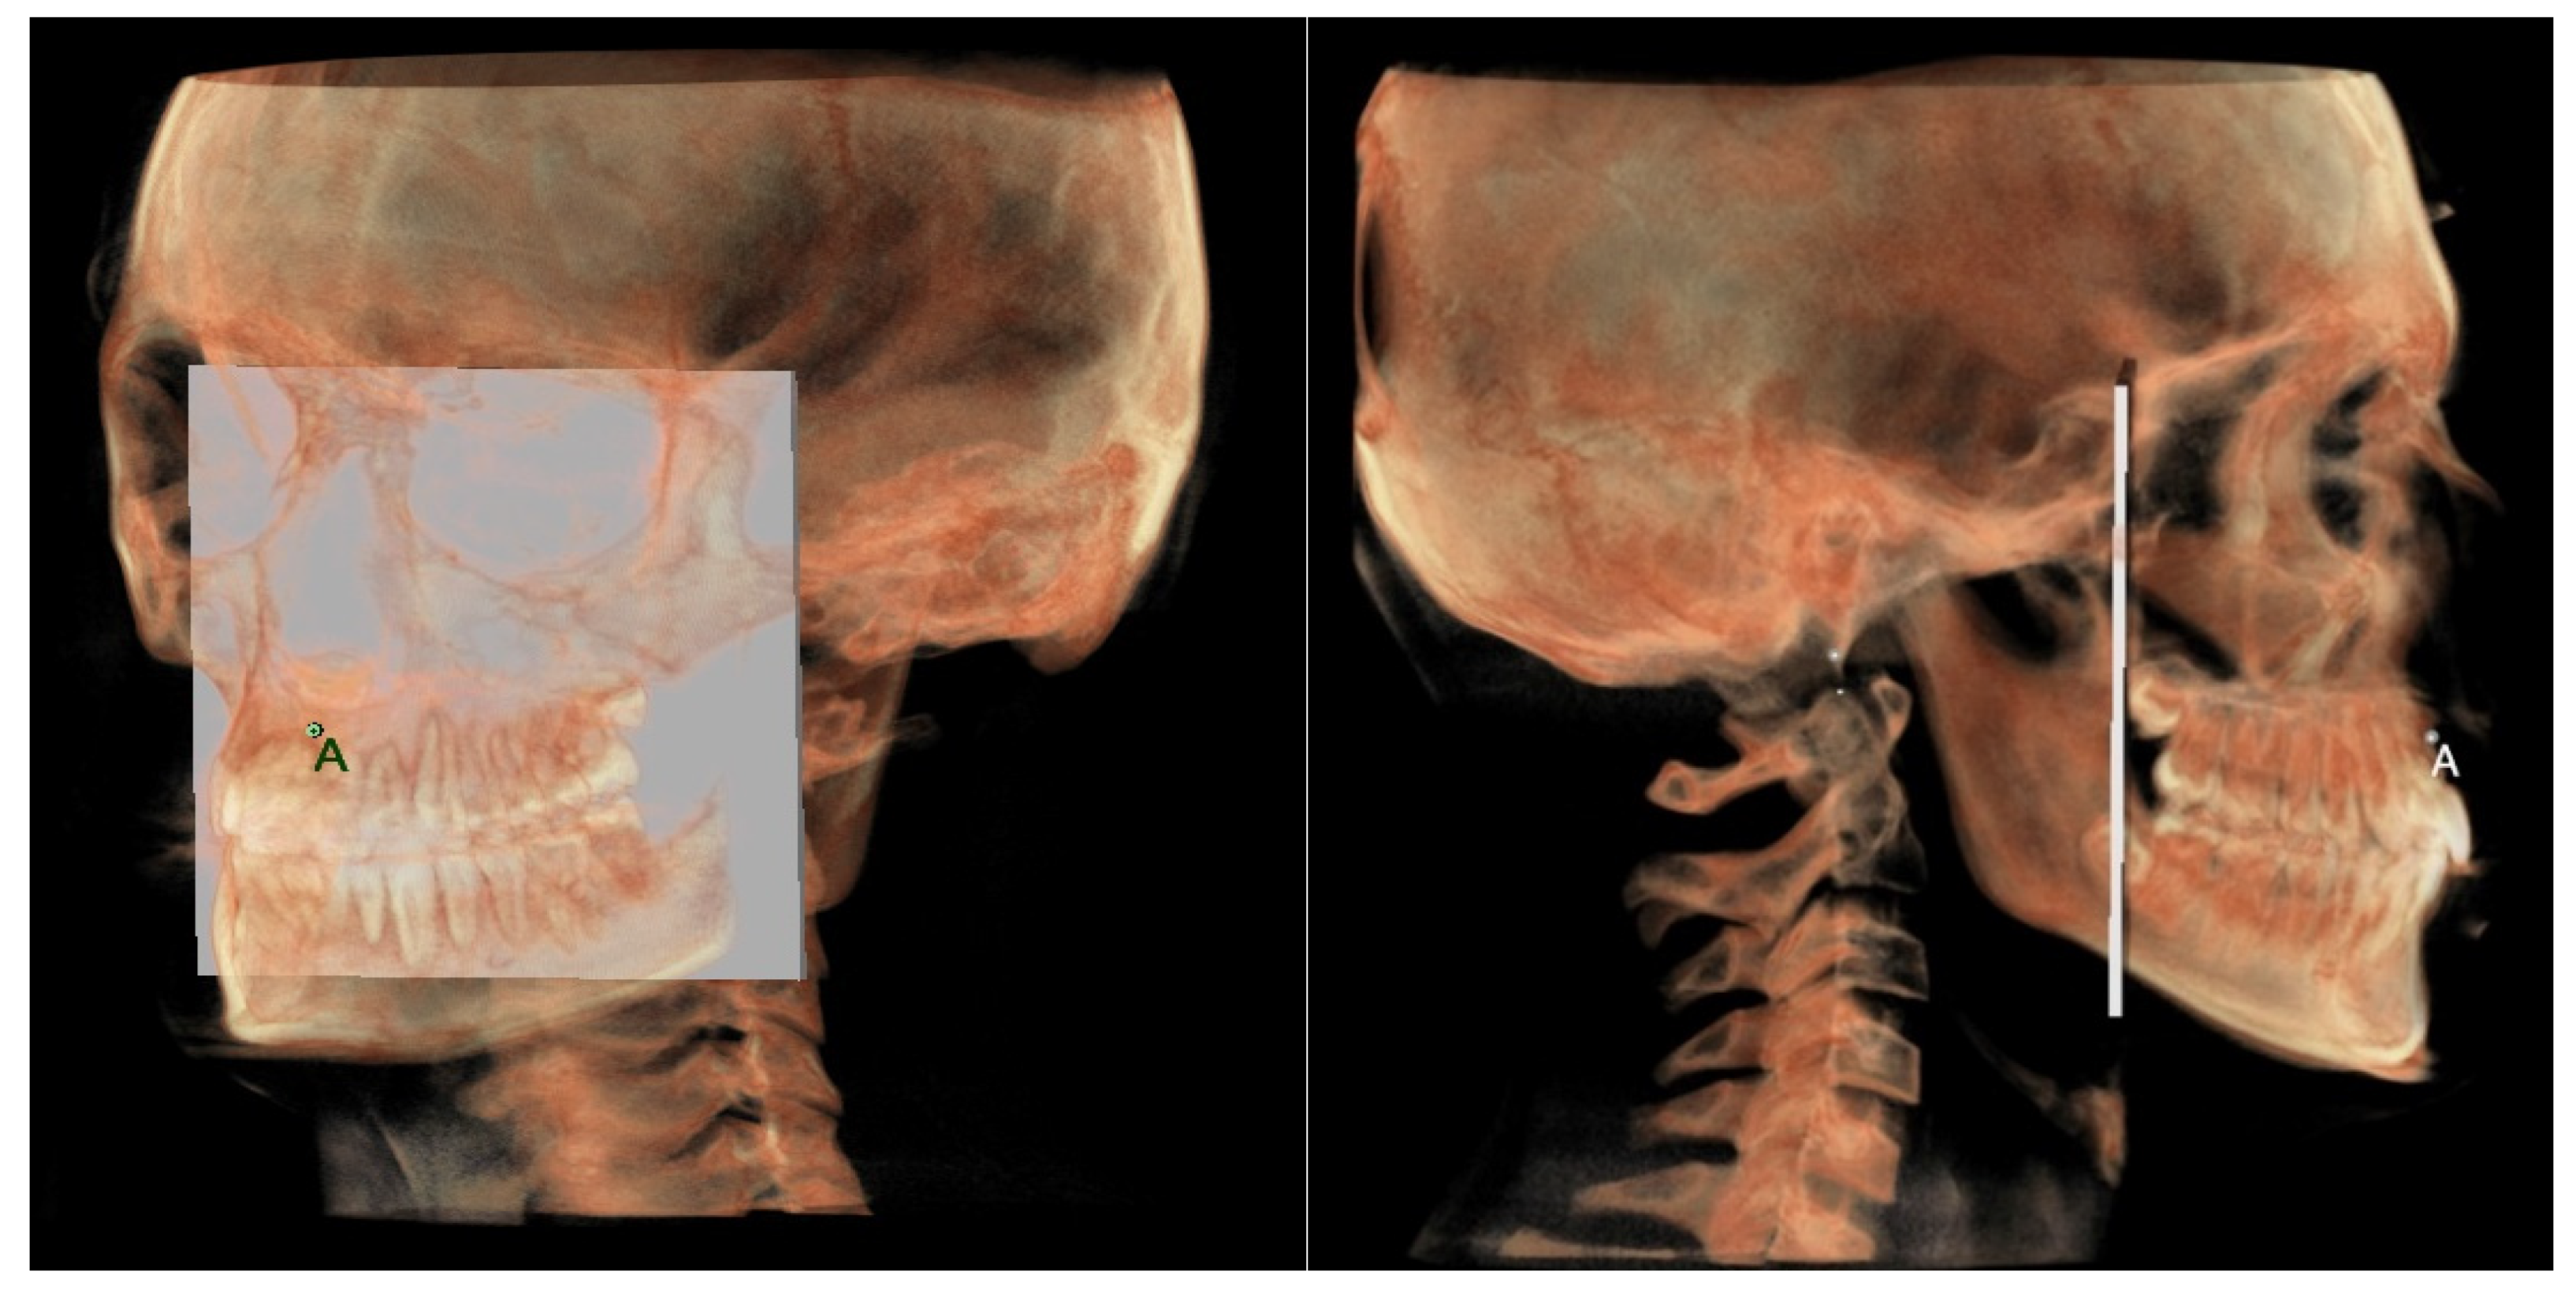

- The maxillary skeletal arch (Figure 6) was measured from point A to a plane passing through the PNS and parallel to the coronal plane.

| A | Most concave point on the midline of anterior maxilla | / | / |